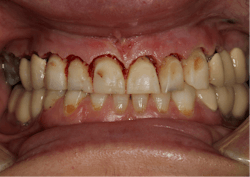

A 35-year-old female patient presented with esthetic concerns after a diagnosis of Sjögren's syndrome. Patient complaints included short appearance of teeth, stained teeth, and worn incisal edges (figures 1–2). Loss of vertical dimension of occlusion was noted as evidenced by shortened coronal structure and bilateral angular cheilitis (figure 3).

Upon clinical and radiographic examination, it was determined that the patient had a combination of caries, inflamed gingiva from desiccation, and loss of vertical dimension (figure 4). Xerostomia and insufficient home care were implicated in the patient’s elevated caries rate, as well as the presence of implants leading to implant-induced caries.